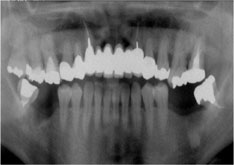

Yさんは長年入れ歯を使っていました。

Yさんは長年入れ歯を使っていました。

多少不自由は感じていたものの、仕事も忙しく、特別何かを変える事は考えてはいませんでした。ところが、ある日入れ歯のバネがかかっている歯が急に痛みだし、顔が腫れてきました。Yさんが、私の所に来てレントゲンを撮ると原因は、バネのかかっている歯の根が弱ってきたためでした。

通常入れ歯の場合、入れ歯を支える歯にバネをかけます。そしてバネがかかっている歯にはかなりの負担がかかるのです

長年負担がかかった歯は、いつかダメになります。

そしてその歯を抜くと次の歯にバネをかけなければなりません。

するとまたその歯がダメになるのです。これは本当によくあるパターンです。

Yさんはバネがかかっている歯を守るために、インプラント治療を選びました。入れ歯の4本の部分にインプラントを入れたのでした。

Yさんはバネがかかっている歯を守るために、インプラント治療を選びました。入れ歯の4本の部分にインプラントを入れたのでした。